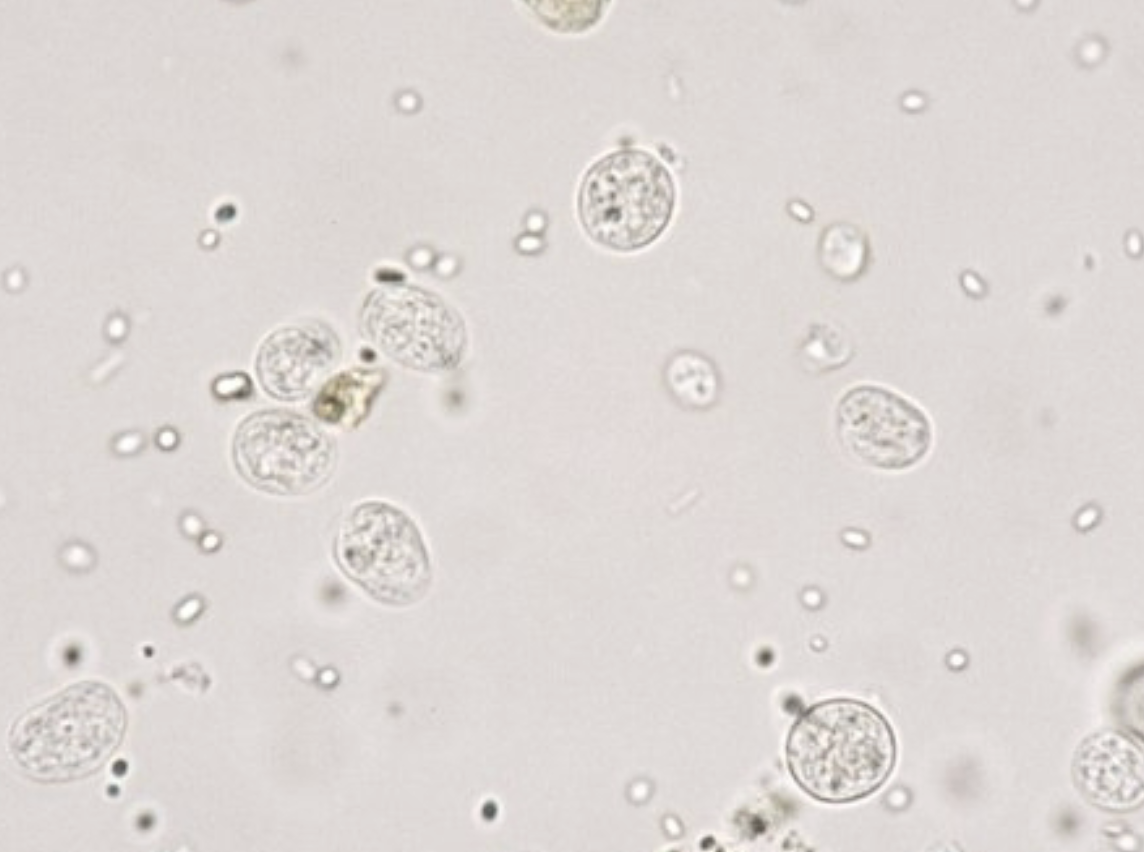

Entamoeba histolytica troph

Entamoeba histolytica troph

Entamoeba histolytica cyst

E. hartmanni troph

E. hartmanni cyst

E. coli troph form

E.coli troph form

E. coli cyst

E.coli cyst